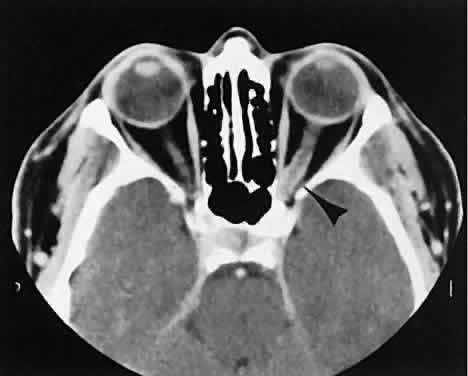

Graves' orbitopathy probably represents the most frequent cause of proptosis and EOM enlargement. The CT findings are fairly stereotyped and typically display various degrees of EOM enlargement (Fig. 7). The inferior rectus muscle usually is affected earliest, followed by the medial rectus, superior rectus, and finally the lateral rectus muscle. Rootman and colleagues13 noted more frequent involvement of the superior rectus/levator and medial rectus muscles than what had been reported previously with Graves' orbitopathy. These muscles can be affected in isolation, with the exception of the lateral rectus. To the best of our knowledge, isolated lateral rectus enlargement has not been reported in Graves' orbitopathy and in our experience usually is associated with a sphenoid wing meningioma.

Fig. 7. Graves' orbitopathy with two variations. Axial (A) and coronal (B) views show symmetric fusiform enlargement of the extraocular muscles with tapered muscle insertions. Note the predominant enlargement of the inferior, medial, and superior rectus muscles with lesser involvement of the lateral rectus muscle, a frequent pattern of enlargement in Graves' orbitopathy. Axial (C) and coronal (D) views of Graves' orbitopathy with expansion of retrobulbar ground substance and relative sparing of the extraocular muscles.

CT evidence of Graves' orbitopathy tends to be bilateral. Approximately 86% of patients with unilateral clinical findings have bilateral CT findings in our experience, which is consistent with the experience of others.42

Morphologically, the EOM belly is enlarged, with a gradual tapering toward and sparing of the tendinous portion of the muscle. Tendon involvement is a typical feature of orbital myositis. Tendon involvement helps to differentiate this lesion from Graves' orbitopathy, although Rootman and Nugent43 have noted a rare patient with Graves' orbitopathy with this finding.

The muscle belly has a smooth contour with no edema of the adjacent orbital fat. We recently evaluated a patient with a referral diagnosis of Graves' orbitopathy. The patient was euthyroid but had severe orbital congestion typical of advanced Graves' orbitopathy. Imaging showed “dirty” orbital fat and lateral rectus muscle morphology that seemed atypical (Fig. 8). Biopsy specimen results showed a low-grade lymphoma. Hypertrophy of the medial rectus muscle can cause the medial wall to bow in toward the ethmoidal sinus from the chronic effects of pressure on the bone. The hypertrophied muscles also can give rise to a compressive optic neuropathy in the orbital apex as the enlarged muscles take their origin from the anulus of Zinn. Axial views of the apex show an apparent mass if the inferior rectus muscle is enlarged. It is imperative that additional views, sagittal or preferably coronal, be obtained to show the true nature of this apparent mass. Intracranial fat prolapse, seen by CT, may be another sign of optic neuropathy.44 An optic neuropathy also can be seen with relatively normal-sized EOM. An expanded fat compartment with optic nerve stretch has been associated with an optic neuropathy.45,46

Fig. 8. Low-grade lymphoma confined to orbit mistaken for Graves' ophthalmopathy in a 65-year-old man. A. On the axial view, orbital fat appears “dirty” with marked increase in soft tissue stranding. Muscles do not have a smooth appearance, lateral rectus muscles have lumpy appearance (arrow), and both lateral rectus muscles are disproportionately large for what typically is seen in Graves' orbitopathy. B. Coronal view also shows dirty orbital fat. Note left inferior rectus, which is small (arrowhead), and also is atypical in Graves' orbitopathy when there is enlargement of the other extraocular muscles.